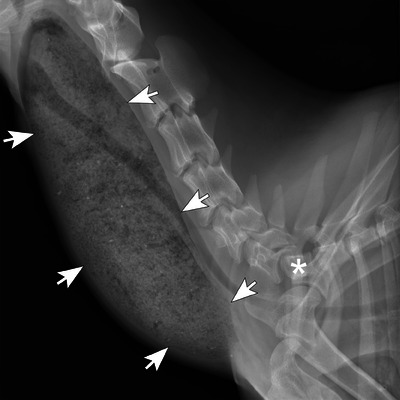

一个4岁的尼日利亚侏儒提出慢性反流和颈部肿胀的三年持续时间。体格检查发现颈部腹侧有一个大肿块。山羊多次尝试吞咽和反刍,但肿块的大小没有明显变化。颈椎x线片显示食道节段性扩张至胸入口水平。CT显示过渡性第七颈椎伴左右肋骨融合,导致食管外压迫和胸入口水平梗阻。这是山羊颈肋引起食管肥大的第一个报告。

A 4-year-old Nigerian Dwarf wether presented for chronic regurgitation and cervical swelling of three years duration. Physical examination revealed a large ventral cervical mass. The goat made repeated attempts to swallow and regurgitate, but the mass did not change significantly in size. Cervical radiographs revealed segmental esophageal dilation to the level of the thoracic inlet. CT revealed a transitional seventh cervical vertebra with fused right and left ribs, resulting in extramural esophageal compression and obstruction at the level of the thoracic inlet. This is the first report of a cervical rib causing megaesophagus in a goat.